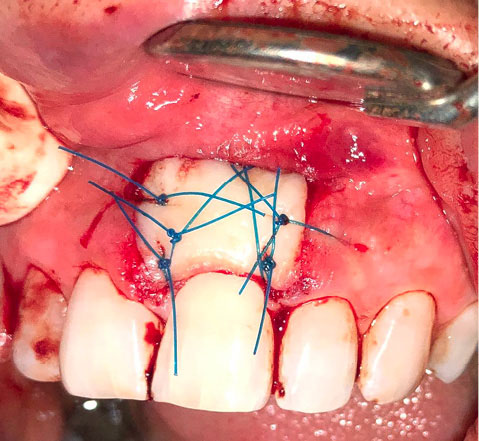

The surgery was performed under local anesthesia with 2% lidocaine and epinephrine at a concentration of 1:100,000. The excision of the lesion was instituted with a #15C blade. The lesion and the involved periodontal tissue were removed, followed by thorough curettage of the underlying bone and root planing of the tooth (Figure 2).

japid-12-95-g002

Figure 2. Periodontal defect after excision and curettage (recipient site).

After the excision, the lesion was taken with fine tissue forceps and transferred to a specimen bottle containing 10% neutral buffered formalin with almost 20 times the sample’s volume. A biopsy data sheet was completed, and the specimen was delivered to the laboratory.

A free gingival graft was harvested from the palate to place in the exposed area to regenerate the lost periodontal tissue due to the excision.

A sterile aluminum foil template of the recipient site was made to be used as a pattern for harvesting the graft from the palate. The template was placed over the donor site, and a shallow incision was made around it perpendicular to the tissue with a #15 blade (#15 blade was selected due to its wider tip because we only needed the tip of the blade) (Figure 3).